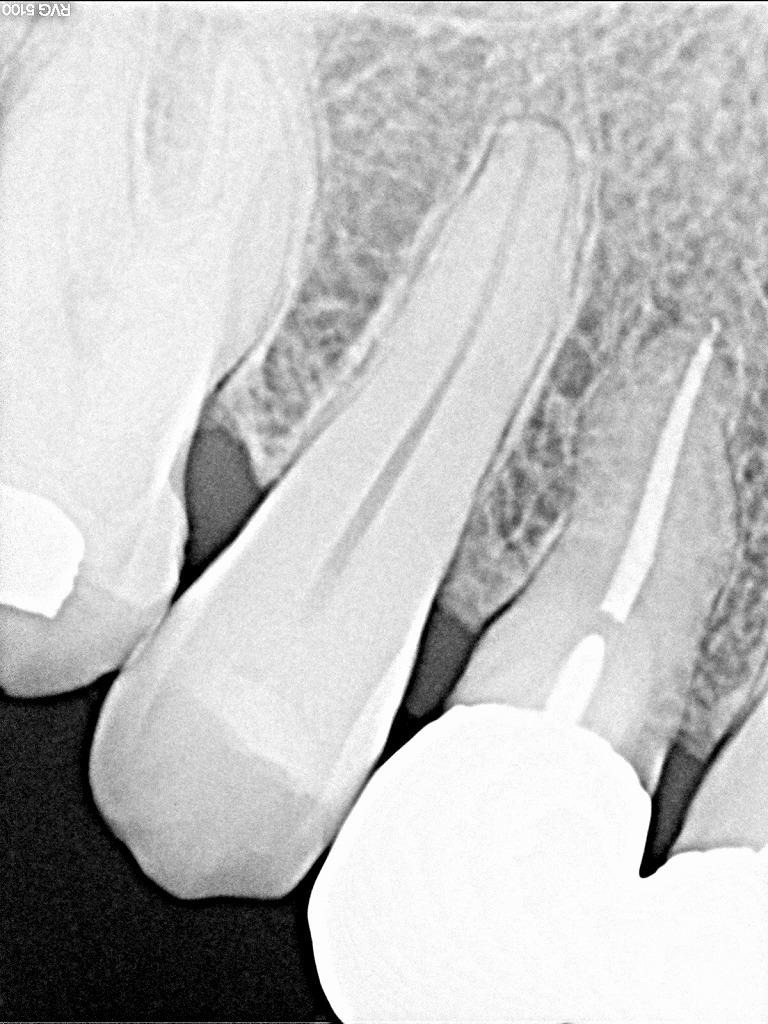

歯石を除去していくと同時に4番部の根を調べていきます

頬側根が完全に骨内に埋まっていませんでした

頬側根をヘミセクションしてCR樹脂にて充填しています